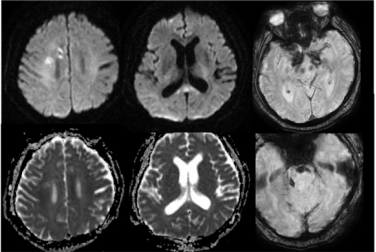

2024年9月22日,患者发热、头痛(当时甲泼尼龙减至40 mg qd口服),双下肢无力明显加重,伴有胡言乱语、精神异常。2024年9月27日,患者意识模糊,颈项强直;脑脊液:压力340 mmH2O,黄色浑浊,白细胞383*106/L,糖1.82 mmol/L↓,氯化物109.4 mmol/L↓,蛋白7.53 g/L↑,宏基因组学二代测序水痘-带状疱疹病毒(VZV)序列数3499,Xpert(-);头颅计算机体层摄影(CT)示幕上幕下脑积水;考虑脑疝,转入ICU行脑室外引流术,予以阿昔洛韦抗病毒、四联抗结核治疗,地塞米松抗炎。2024年10月3日,患者意识好转,头颅MRI示右侧顶枕叶点状、胼胝体压部DWI高信号,ADC减低。2024年10月10日复查腰穿脑脊液压力>400 mmH2O,黄色浑浊,蛋白5.8 g/L↑,白细胞247*106/L,糖7.42 mmol/L,氯化物108.5 mmol/L↓;腰穿后再次脑疝,留置脑室外引流。2024年10月29日转入普通病房,家属发现双耳听力下降,当地考虑中枢神经系统VZV感染、结核感染不除外,予以抗病毒、抗结核、脱水降颅压治疗约1个月,患者头痛好转,精神行为异常明显,双下肢肌力0级。2024年11月5日就诊于我院急诊,头颅增强MRI提示多发性脑梗死(图2)、硬脑膜强化(图3);历次腰穿结果见表1。病来,患者精神、食欲、睡眠欠佳,留置尿管,辅助通便,体重无明显下降。

图2 头颅常规MRI+SWI

头颅MRA:椎动脉(R-VA)、基底动脉(BA)、右大脑中动脉(R-MCA)、右大脑后动脉(R-PCA)多发节段性重度狭窄(图4)。

第一阶段病程:患者亚急性起病,病初为双下肢无力,3个月期间无明显变化,3个月后突然急性加重,不符合急性脊髓炎的病程特点,结合下胸段脊髓长节段长T2信号、水肿明显、脊髓可见可疑的血管流空影,需考虑脊髓血管病。进一步完善颈胸腰椎增强MRI,可见胸髓多发斑片状异常信号、脊膜不均匀增厚伴强化、脊髓周围多发迂曲血管影、脊髓表面含铁血黄素沉积(图6)。脊髓数字减影血管造影(DSA)可见左侧T10肋间动脉造影时早期静脉充盈、迂曲扩张,考虑为硬脊膜动静脉瘘(SDAVF)可能大(图7)。治疗方面,于神经外科行硬脊膜动静脉瘘切除术。

第二阶段病程:大剂量激素冲击治疗后出现发热、头痛、精神行为异常,腰穿脑脊液白细胞明显升高,考虑免疫抑制后继发感染性脑膜脑炎。脑脊液宏基因组学二代测序VZV序列数高,经抗病毒治疗后颅压、白细胞、蛋白及VZV序列数均明显下降,支持中枢神经系统VZV感染。此外,患者脑脊液蛋白显著升高,糖、氯化物降低,血结核感染特异性T细胞检测阳性,影像上脊膜增厚明显,需考虑合并中枢神经系统结核感染不除外。患者多发性脑梗死、局部蛛网膜下腔出血,颅内动脉多发节段性中重度狭窄,需考虑合并感染性血管炎可能。治疗方面,予以足量、足疗程抗病毒治疗及抗结核治疗。